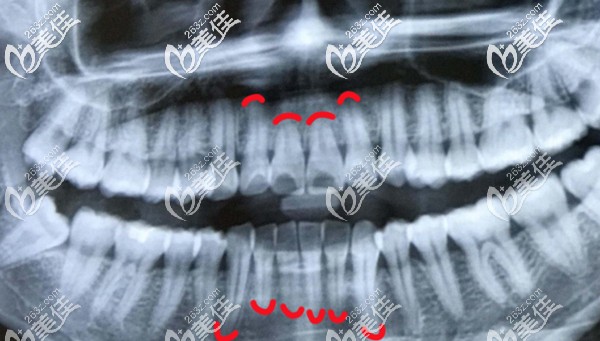

這張全景片的顧客,也是先天性牙根短,不過已經(jīng)成功完成正畸了。不知道你的情況和她變比,差距大不,若比她的牙根還短許多,那就要慎重考慮是否要做矯正了,畢竟牙齒健康更重要嘛。

你好,你有片子嗎,可以傳上來,我?guī)湍惴治鱿?。不然,也不清楚具體情況,具體牙根有多短,到什么程度,是否適合正畸......